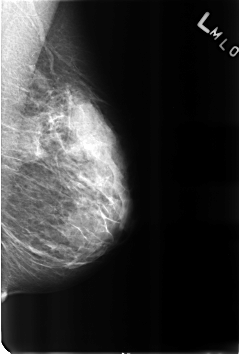

B_3184_1.LEFT_MLO

LEFT_MLO LINES 4592 PIXELS_PER_LINE 3104 BITS_PER_PIXEL 12 RESOLUTION 50 NON_OVERLAY